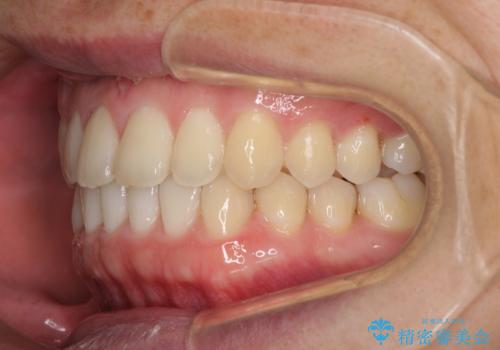

すきっ歯の改善 インビザライン矯正治療

- 上の前歯の隙間を気にして来院された患者様です。

インビザラインにより、上下の歯列を側方に拡大しつつ、前歯の隙間を閉じていくこととしました。

1日22時間の装着時間をしっかりと守ってくださったので、隙間がきれいに閉じ、口元の突出感も改善することができました。